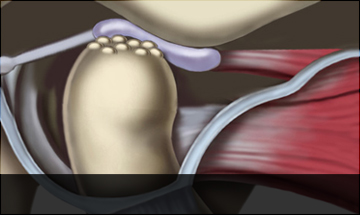

턱관절 디스크의 위치는 정상적이고, 턱뼈에도 이상이 없는

상태입니다. 턱을 열고 닫을 때 불편감을 느끼지만,

턱관절에서 소리가 나지 않고 통증도 심하지 않은

경우입니다. 대개 약 2주에서 1개월 정도의 치료로

좋아지는 경우가 많습니다.

정상디스크 위치

입을 다물고 있는 상태

입을 열고 있는 상태

정상 디스크 위치